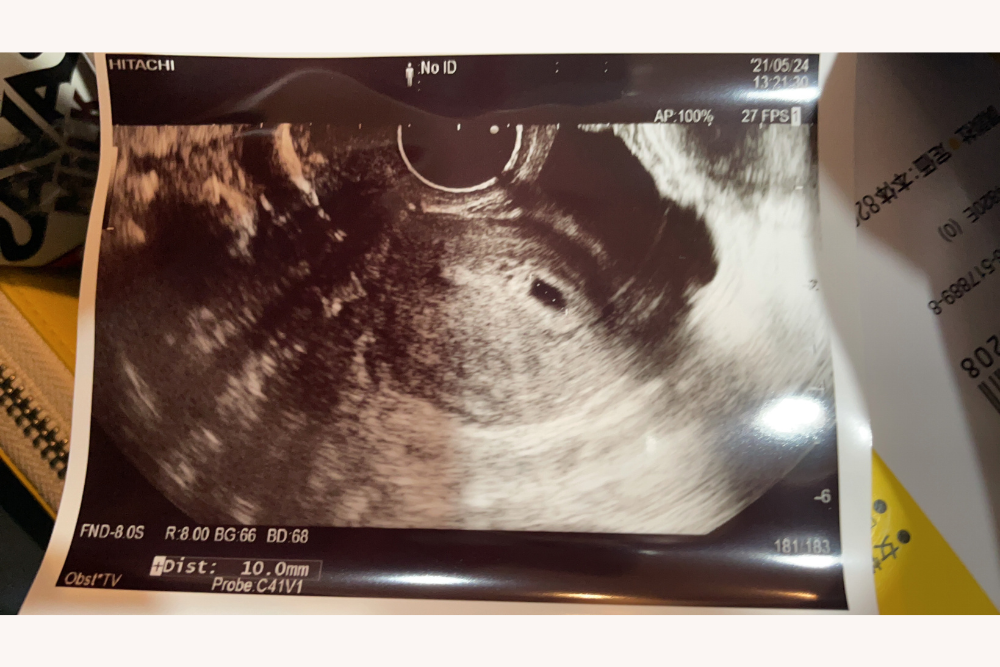

妊娠がわかったのは、不妊かも?と最初に病院にかかってから約2年後。採卵は4回行いましたが、幸いなことに、初めての移植で着床して妊娠できました。

娘がおなかにやって来てくれました。